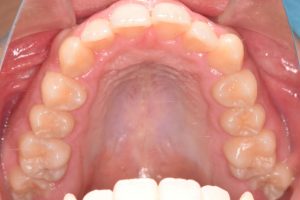

2期治療開始時(2023年7月)と装置撤去時(2025年9月)の写真です。

上あご